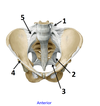

4? 5?

7? 8?

3? 4?

1? 2?

1? 2? 3?

1? 2?

1? 2?

3? 4?